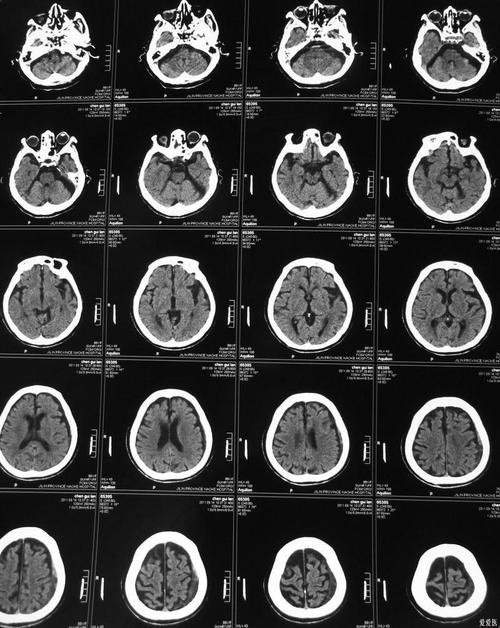

常规的、非增强的脑CT平扫,在脑梗发生的超早期(通常最初6小时内)检出率很低,难以明确诊断,但在发病后的特定时间点,它对诊断脑梗非常有价值。

脑梗死的本质是脑组织缺血、缺氧后坏死,CT影像上,坏死组织与正常脑组织在密度上会有差异,但这种差异的出现需要时间。

A. 超急性期(发病后6小时内)—— 检出率低

这是脑梗治疗的“黄金时间窗”,在这个阶段,由于脑细胞刚刚开始缺血坏死,细胞水肿刚开始,脑组织的密度变化非常微小,常规CT通常看不出明显异常。

B. 急性期(发病后6小时 - 3天)—— 检出率显著提高

随着缺血时间的延长,脑细胞坏死和水肿加重,坏死区域的脑组织密度会开始下降。

- 低密度灶: 在CT图像上,梗死区域会呈现为低密度(发黑)的阴影,这是因为坏死的脑组织水分含量增加,密度低于周围正常脑组织。

- 占位效应: 如果梗死面积较大,周围脑组织会发生明显水肿,导致脑室受压变形,中线结构移位。

在这个时间段,CT是诊断脑梗的重要和常用工具,能清晰显示梗死的位置、范围和严重程度。

C. 亚急性期(发病后4天 - 3周)—— 检出率最高

这个阶段是CT显示脑梗死最清晰的时期,脑水肿达到顶峰后开始消退,而坏死组织与正常组织的密度差异达到最大。

- 明显的低密度灶: 梗死灶边界变得非常清晰,呈均匀的低密度。

- “模糊效应”: 大约在发病后2-3周,坏死组织开始被吞噬细胞清除,密度可能暂时与正常脑组织相近,导致边界模糊,但这仍然是梗死的表现。